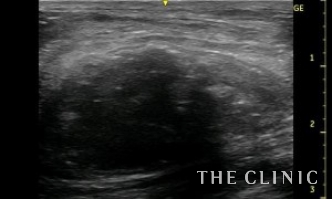

ほとんど内容物は消失しました。2か月後にしこりの部位が硬くなったため来院するとしこりの被膜内にリンパ液が貯留していました。